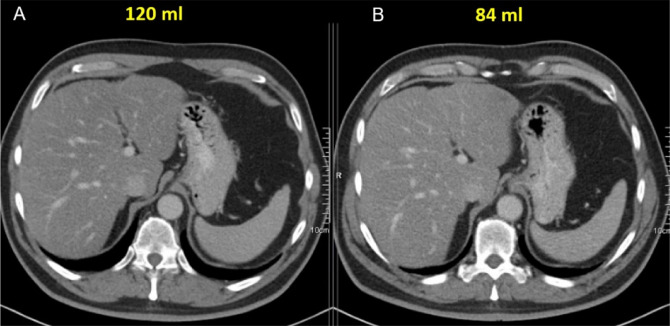

Objectives: to determine (1) a target Hounsfield unit (HU) for portal venous phase iodinated contrast media enhanced abdominal CT scans, (2) an equation for a personalized total contrast agent volume, and (3) the best/most appropriate time between injection and plateau/peak in HU enhancement. Material and methods: from an original dataset of 5,000 cases, a weight representative subset of 370 cases was sampled for detailed HU measurements. An additional 90 cases were used for visual grading to define the minimal HU required for diagnostic quality, which led to the proposed target HU. This study uses the fact that in a first approach, the injected contrast agent volume and HU correlate linearly. Based on the injected contrast agent volumes and HU measurements in the patient scans, it was then calculated which (ideal) volume would have reached the target value. The ideal volumes and patient data (weight, height, heart rate, age, and gender) were correlated by means of a regression analysis, to determine a new patient-specific contrast volume calculation equation. The best scan delay time was derived from the start of the injection to the HU enhancement plateau/peak evaluated from manually triggered venous phase scans. Results: The target HU value was 125. This can be achieved with a personalized contrast agent volume (ml), equal to - 108.5 + ∗ weight(kg) + 0.40 ∗ heart rate(bpm) + 0.61 ∗ height(cm). The time delay between injection and HU plateau/peak was found to be, on average, 102 s. Conclusion: this study proposes a comprehensive protocol for contrast enhanced venous phase scans, including a target HU, a personalized contrast volume, and a scan delay.